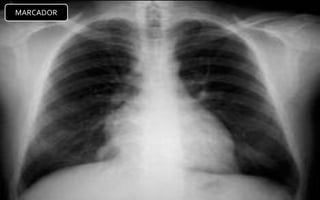

CASOS PATOLOGICOS

1. Aumento del índice

cardiotorácico.

2. APEX se dirige hacia abajo del

diafragma por dilatación delVI.

3. Aumento de la densidad

pulmonar bilateral con

distribución perihiliar y basal,

aspecto algodonoso,

confluente, límites mal

definidos borrosidad vascular

(InfiltradoAlveolar).